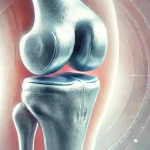

ایمپلنت زانو نوعی پروتز پزشکی است که جایگزین مفصل آسیبدیده زانو میشود. این روش برای افرادی توصیه میشود که در اثر آرتروز شدید، آسیبهای ورزشی یا تصادفات، عملکرد طبیعی زانوی خود را از دست دادهاند.

ایمپلنتها از مواد مقاومی مانند تیتانیوم، آلیاژهای فلزی و پلیاتیلن ساخته میشوند تا بتوانند فشارهای روزمره بر روی زانو را تحمل کنند.